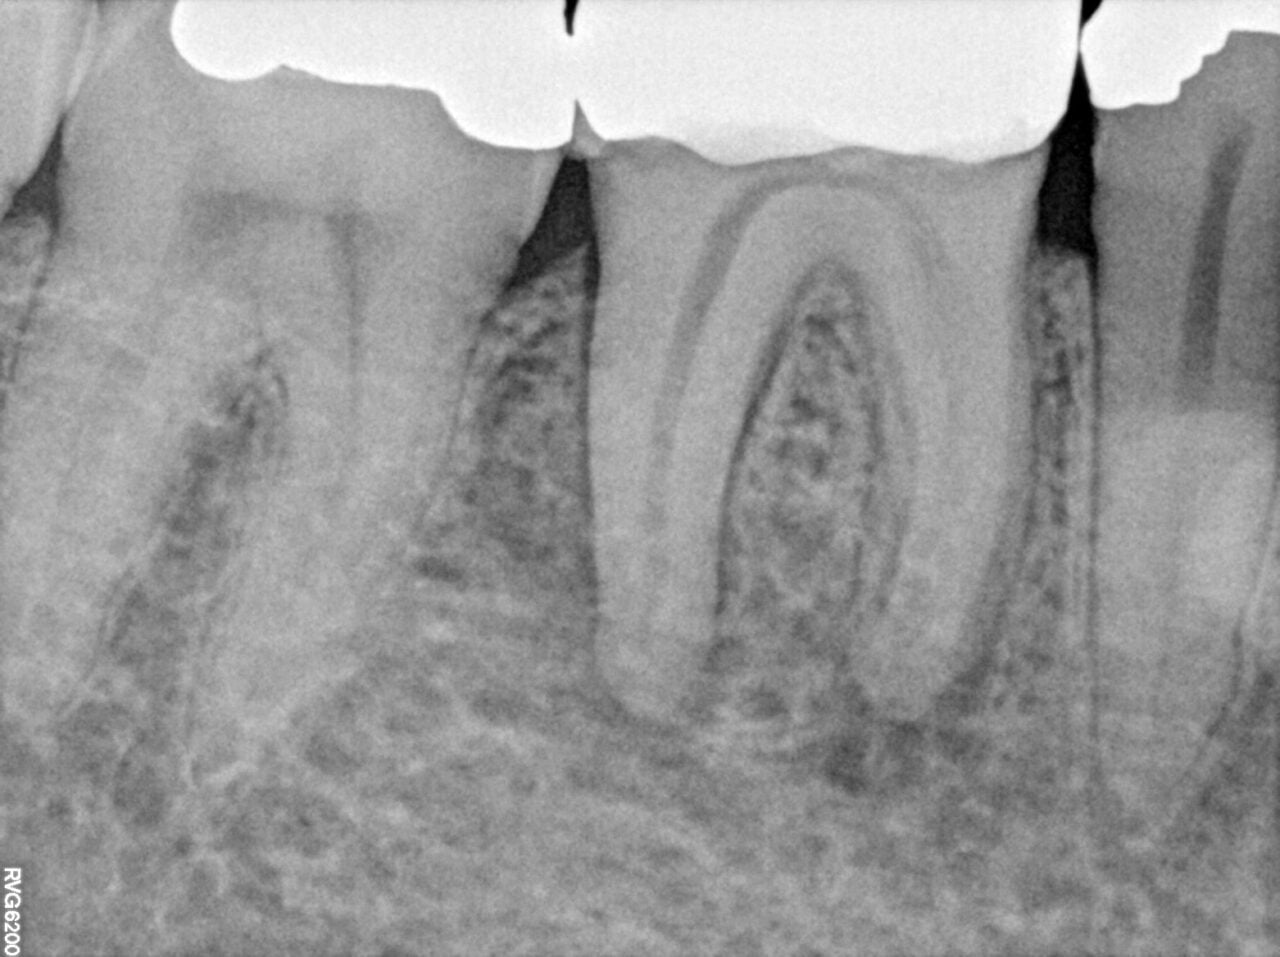

Radiograph of the teeth before endodontic treatment

The first patient was referred to Dr. Michiels in June 2023. A deep restoration had previously been performed on the mesial surface, and the attending dentist determined that a root canal treatment was required. However, at the initial consultation, the tooth still tested vital and the patient had no symptoms.

A few months later, the patient reported increasing pressure pain. The diagnosis then evolved to pulpal necrosis following the deep restoration, accompanied by acute symptomatic apical periodontitis, confirming that root canal therapy had become unavoidable.

Because the affected tooth was the upper left second molar, visibility was already limited. The challenge was further increased by the patient’s restricted mouth opening, which made the entire procedure more demanding from a practical standpoint.